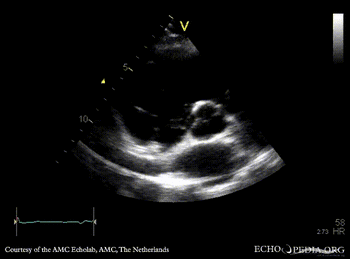

Case 48